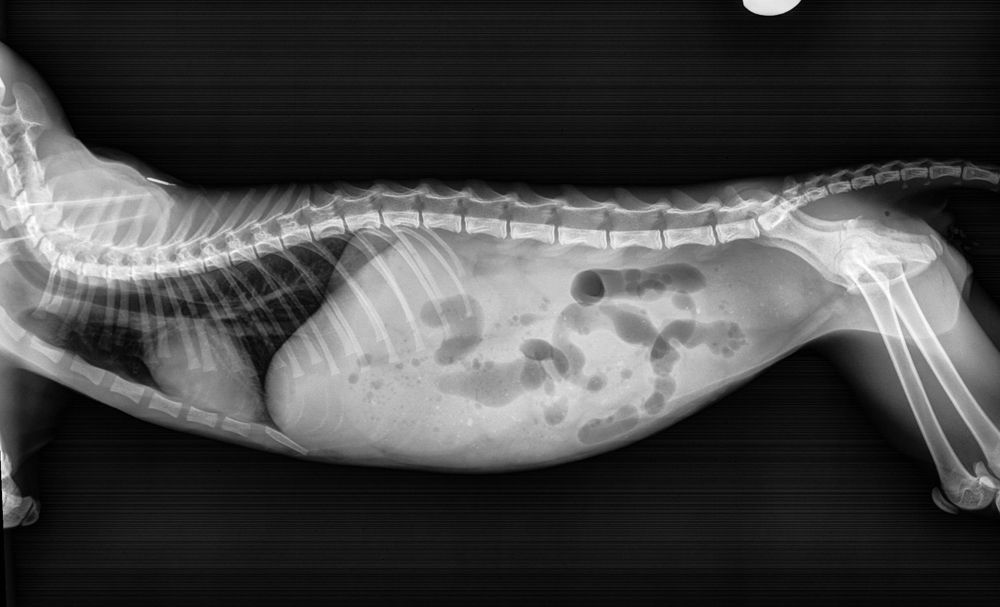

But it soon became clear the little cat was suffering terribly with severe constipation, prompting her to take him for X rays of his colon, after which vets told Ginevra her 'Tom' cat looked more like a queen – leading her to rename the animal Garie-Ann.

But when, within a few days, he became worryingly constipated, she feared he had a condition called megacolon – an abnormal dilation of the large intestine.

Taking him with her to work, her colleagues performed another X ray, revealing that he was seriously constipated once again.